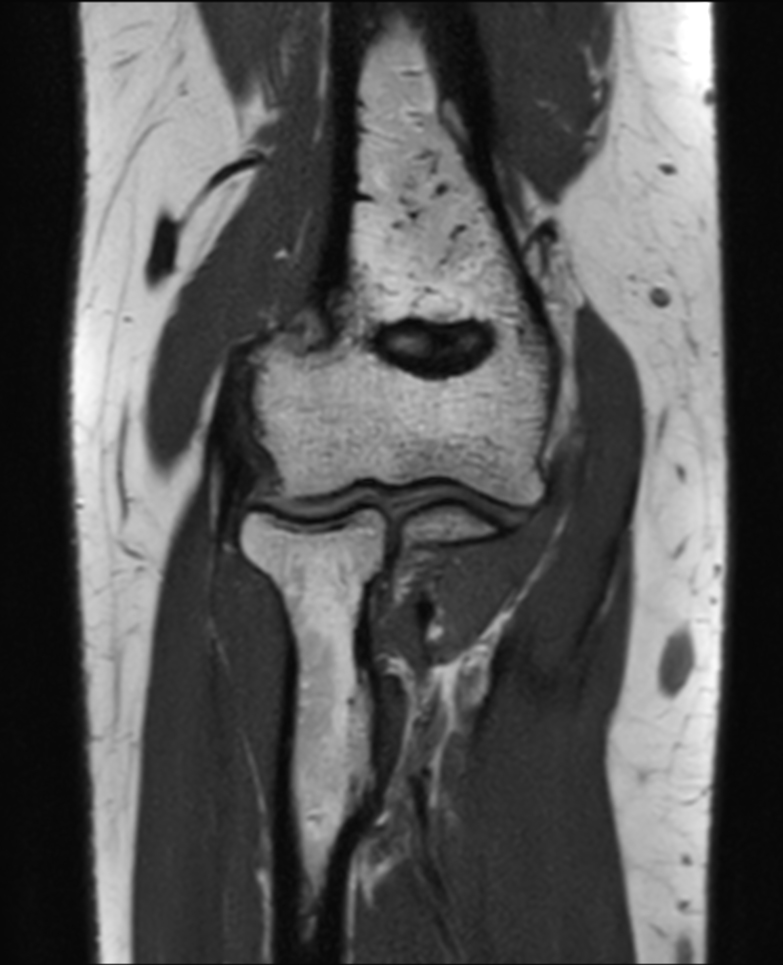

Large FOV imaging with the dS 16ch Small Extremity coil

Used Solution

• System

• Coil

• Clinical Application